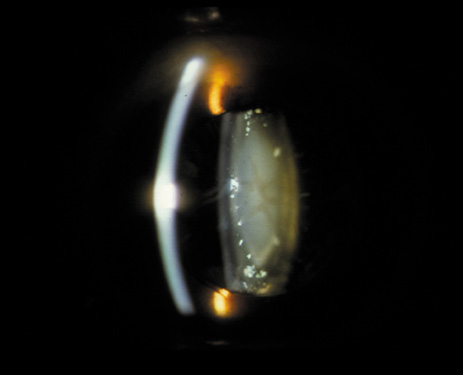

One can examine this type of cataract with direct illumination, using the narrow and broad beams of the slit-lamp to show the characteristic granular inner surface immediately in front of the posterior capsule (Fig. 13). The problem with this technique, however, is that patients may not tolerate any prolonged direct illumination because of the glare. Retroillumination is therefore more useful for revealing the outline of the opacity, since it is usually seen as an “island” in the center of the posterior capsule, which is further highlighted by the shadow cast by the opacities.33 However, in the early stages of this type of cataract, the dust-like particles that might be noticeable in the central posterior subcapsular area with direct illumination disappear or are difficult to see with retroillumination (Fig. 14). Eventually this “dusting” becomes dense enough to cast a shadow and thus appear on retroillumination. The smooth orange background of the fundus helps to highlight the rough, irregular pseudopodia-like edges of the central opacity. In advanced stages, the PSC may become a thick, calcified plaque (Fig. 15). During surgery, excessively vigorous scraping or vacuuming of the calcified opacity can lead to rupture of the posterior capsule. Usually, small remnants that are left behind after surgery are reabsorbed and do not interfere with vision; otherwise, they are easily treated with a neodymium : yttrium (Nd:YAG) aluminum garnet laser. Pathologic evidence suggests that most PSCs result from the migration of bow region cells into the potential space (along with accumulated cellular debris) between the posterior capsule and the cortex.34–36

Fig. 14. A PSC, showing vacuoles and dust-like material in the potential space between the posterior cortex and the capsule.